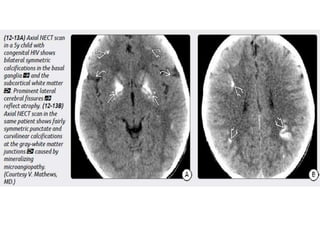

Congenital (Perinatal) HIV

Imaging

Atrophy, particularly in the frontal lobes.

Bilaterally symmetric basal ganglia calcifications.

Ectasia and fusiform enlargement of intracranial arteries.

Strokes with foci of restricted diffusion and subarachnoid hemorrhage

may occur as complications of the underlying vasculopathy.

Congenital (Perinatal) HIV Imaging Atrophy,particularly in the frontal lobes. Bilaterally symmetric basal ganglia calcifications. Ectasia and fusiform enlargement of intracranial arteries. Strokes with foci of restricted diffusion and subarachnoid hemorrhage may occur as complications of the underlying vasculopathy.